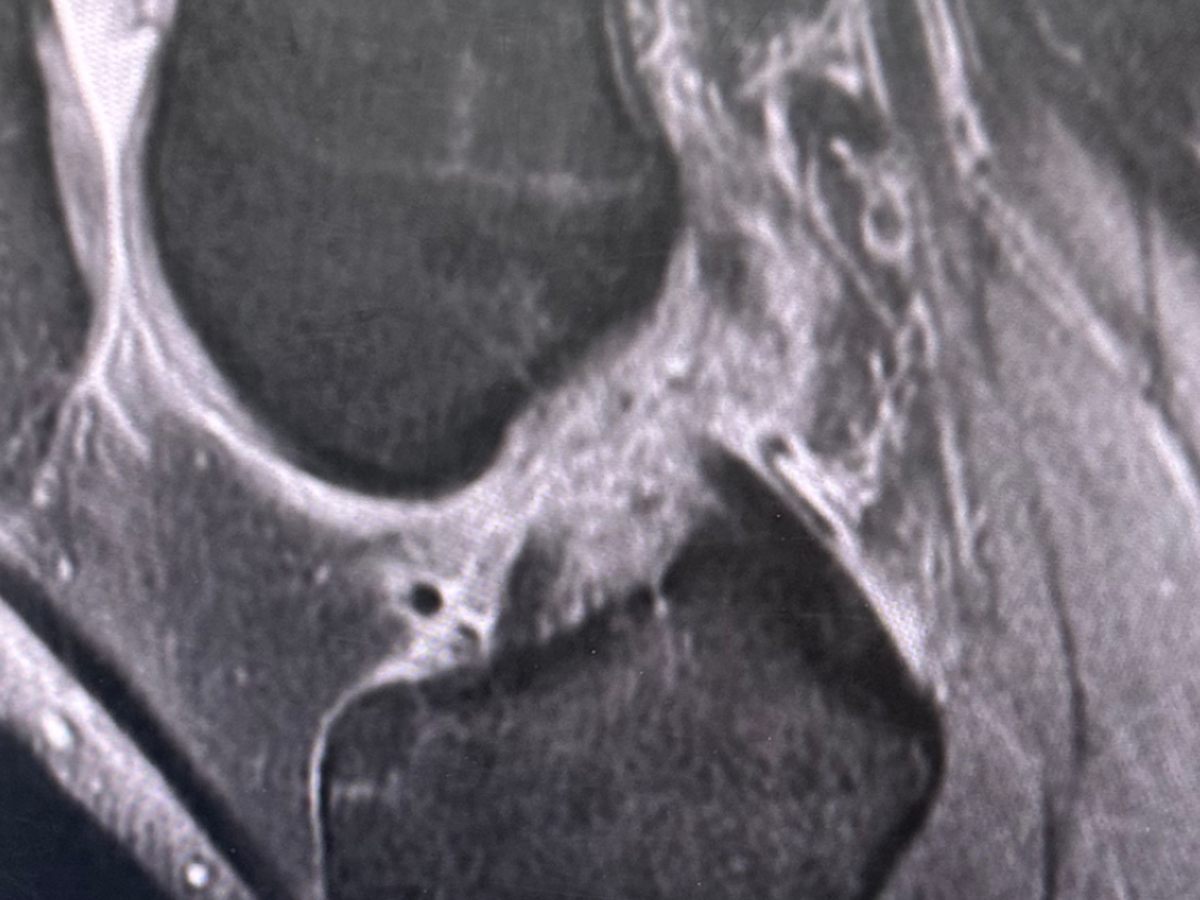

Hi, my name is Sasha and I’m currently facing a challenging medical situation. Three weeks ago I injured my knee and recent MRI scans revealed that I unfortunately have a complete tear of my ACL, damage to both sides of my meniscus, and an injury of my MCL.